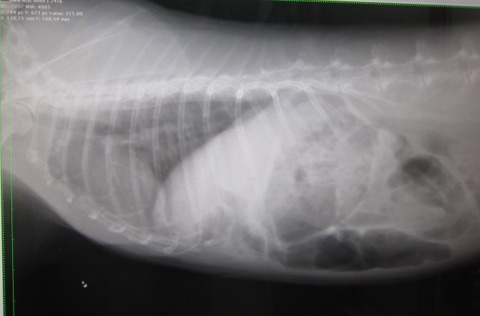

おやすみ前のおやつ、リンゴに反応せず、他のおやつにも反応せず、急変か。

夜の部屋んぽ後は普通やったし、糞もいくらか出てる。

茶々は時々体をゆがめてケージ内あちこち動く

半ば耳が冷たくなる時もあった。

明け方、動きはおさまり耳もぬるめ、呼吸も落ち着いてきたように思えたが

体を歪ませ表情はまだ強張ってる感じ。

6時回って、さ、朝イチ病院に備えて準備、て、してたら急に復活!?